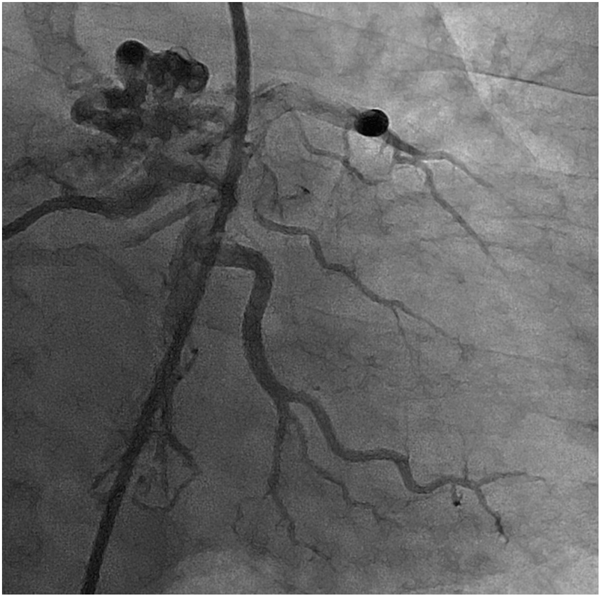

冠動脈でも同様に血管の拡張・蛇行,新生血管の増生がみられるが,冠血流予備能は低下する(図4, 5).

Pediatric Cardiology and Cardiac Surgery 31(3): 95-101 (2015)

図4 左冠動脈の拡張と新生血管がみられる

図5 右冠動脈の拡張と蛇行がみられる